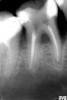

x3m Опубликовано 3 февраля, 2011 Поделиться Опубликовано 3 февраля, 2011 (изменено) вы радуйтесь, что пациентка отказалась, там возможно трещина то уже была, разобрали бы - потом устали бы объяснять, что это уже на удаление. или хуже того, могли и не заметить трещину, тогда бы уже ваша вкладка его добила, еще больше бы устали все объяснять пациентке.возможно, трещина и была. не знаю.пац чистит зубы по 5 раз в день - на работе полный гиг.набор , был плановый профосмотр. жаловалась на запах изо рта. Это было 03.03.непомнюкакогогода осмотрел все. каждый зуб. добрался до миндалин. нашел несколько небольших моментов по зубам и зубным отложениям - в т.ч. и этот.не люблю я анкера. первое, о чем думаю, видя анкер на снимке - "а нет ли трещины". посему покрасил по краю, пощупал зондом - все ок, пощупал ниткой - дистально цепляла за край коронки.честно объяснил о расцементировке/нависающем крае => механике нагрузок => возможном расколе зуба. потом было посещение с жалобами о дискомфорте. 19.06.ХХХХг. Вот здесь уже есть трещина. прокрасилась тоненькая ниточка вестибулярно. зуб предложен на вынос. пац не согласилась.на снимке - такое (см. межзубную перегородку 43-44):http://s59.radikal.ru/i163/1102/60/fc6259cfb206.jpg и на следующем профосмотре (15.09.ХХХХ) - прошло полгода с марта - небольшая рецессия этап разборки гомбозита:http://i019.radikal.ru/1102/05/4e3cf20705a3.jpgи рентгендиагностика линии перелома для наглядности пациенту (была просьба сохранить зуПь):http://s56.radikal.ru/i153/1102/49/9250fb333005.jpg а о трещине спорить не хочу. думаю, в марте ее не было.главное, о чем хотел сказать - после длительного срока службы рентгенологически благополучный активный штифт привел к потере зуба.при таком же исполнении у ВКВ с удлинением клин.коронки в апроксимальных областях этого не произошло бы. имхо. зы. наука прошла бесследно - 45 зуб без ВКВ и коронки до сих пор можно я скопирую и буду особо "экономных" и "самивсезнающих" пацев пугать? конечно я тоже копирую иногда интересные моменты и пугаю пациентов Основная ее часть концентрируется в цервикальной области. Феррул предупредит возникновение экстремальных напряжений, независимо, культевая вкладка это или стандартный штифт. я о ферруле не спорю - безусловно, чем он больше, тем лучше.интересные исследования подтверждены фоткой Снежаны - там, где 13 и 23 зубы по-разному выглядят при использовании гомбозита и активного штифта с разными высотами феррула феррул позволяет частично (!) разгрузить штифт. А не предупредить экстремальные нагрузки.штифт работает в принципе рычага. он не может быть нефункциональным.интересно ведь не только, где и как возникают нагрузки.намного важнее, сможет ли противостоять первичной нагрузке материал, а затем - куда и в каком объеме возникшие напряжения передаются, как гасятся, а где и благодаря чему усиливаются (на апикальных частях, вершинах резьбовой нарезки и т.д) и как реагирует цементный шов и стенки корня. Изменено 3 февраля, 2011 пользователем x3m Ссылка на комментарий